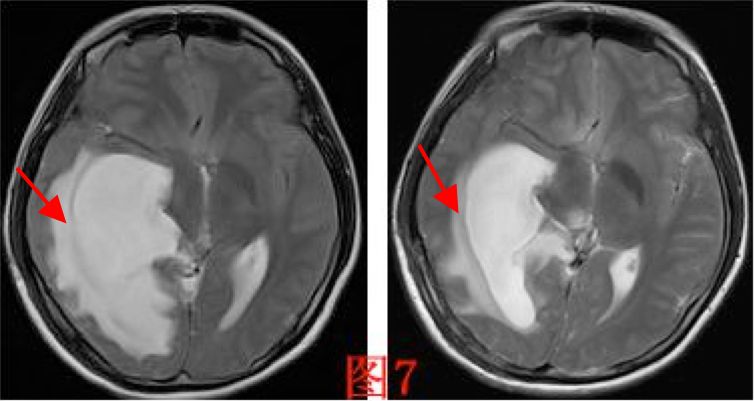

孤立颞角综合征(entrapped temporal hornsyndrome)在1947年由CAIRNS等首次报道[2],目前文献报道少[1, 3-7]。侧脑室三角区是颞角的流出道,解剖位置相对狭窄[8]。当因肿瘤、出血、感染等疾病导致三角区梗阻时,颞角的脉络丛仍持续分泌脑脊液,局部脑脊液积聚,引起颞角扩张,影像学上表现为侧脑室三角区呈气球样膨胀,周围的间质水肿明显,呈“日环征”[2]。本病例图7箭头所指。本病例考虑为手术切除肿瘤后侧脑室三角区少量出血后粘连,并局部脑室外引流管过度引流后导致三角区封闭后引起。

图7. 磁共振表现为侧脑室三角区呈气球样膨胀,周围的间质水肿呈“日环征”